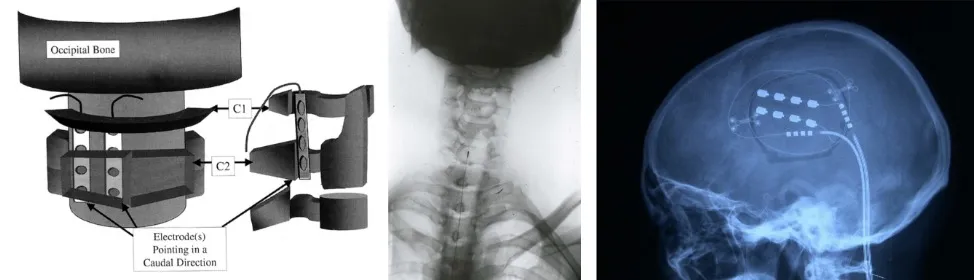

La neuroestimulación representa el paradigma actual del tratamiento neuroquirúrgico del dolor, basándose en el principio de la teoría de la compuerta. En lugar de destruir estructuras nerviosas, estas técnicas modulan la actividad neuronal mediante estimulación eléctrica, siendo reversibles y ajustables.

La estimulación de nervios periféricos y raíces nerviosas constituye la opción menos invasiva, colocando electrodos sobre nervios específicos o raíces dorsales para generar parestesias que enmascaran el dolor en el territorio correspondiente.

La estimulación medular (spinal cord stimulation, SCS) representa la técnica de neuromodulación más utilizada. Se implantan electrodos en el espacio epidural sobre los cordones posteriores, estimulando las fibras Aβ del tacto. Esta estimulación cierra la compuerta del dolor en el asta posterior medular. Resulta particularmente efectiva en síndrome postlaminectomía, dolor neuropático de extremidades y neuropatías periféricas. Los sistemas modernos incluyen múltiples programas de estimulación y la capacidad de estimulación de alta frecuencia.

La estimulación cerebral profunda se utiliza para dolores refractarios, con diferentes dianas según el tipo de dolor. La estimulación de VPM-VPL (núcleos ventral posteromedial y posterolateral del tálamo) resulta efectiva para dolor neuropático con componente discriminativo preservado. La estimulación de PAG-PVG (sustancia gris periacueductal y periventricular) activa sistemas descendentes de control del dolor, siendo útil para dolor nociceptivo refractario.

Más recientemente, la estimulación del córtex motor se ha desarrollado como alternativa para dolor neuropático central, particularmente efectiva en dolor post-ictus y dolor facial neuropático. La estimulación cortical parece modular circuitos talámicos mediante proyecciones córtico-talámicas.

La estimulación del hipotálamo se ha explorado experimentalmente para cefaleas en racimos refractarias, aunque su uso permanece limitado a centros muy especializados.

Las ventajas de la neuroestimulación incluyen su reversibilidad, ajustabilidad de parámetros y menor riesgo de generar dolor neuropático iatrogénico. Sin embargo, requieren implantación de dispositivos, tienen costes iniciales elevados y necesitan recambios de batería periódicos. La selección adecuada de pacientes mediante pruebas de estimulación temporal resulta crucial para identificar quiénes se beneficiarán de estos tratamientos.